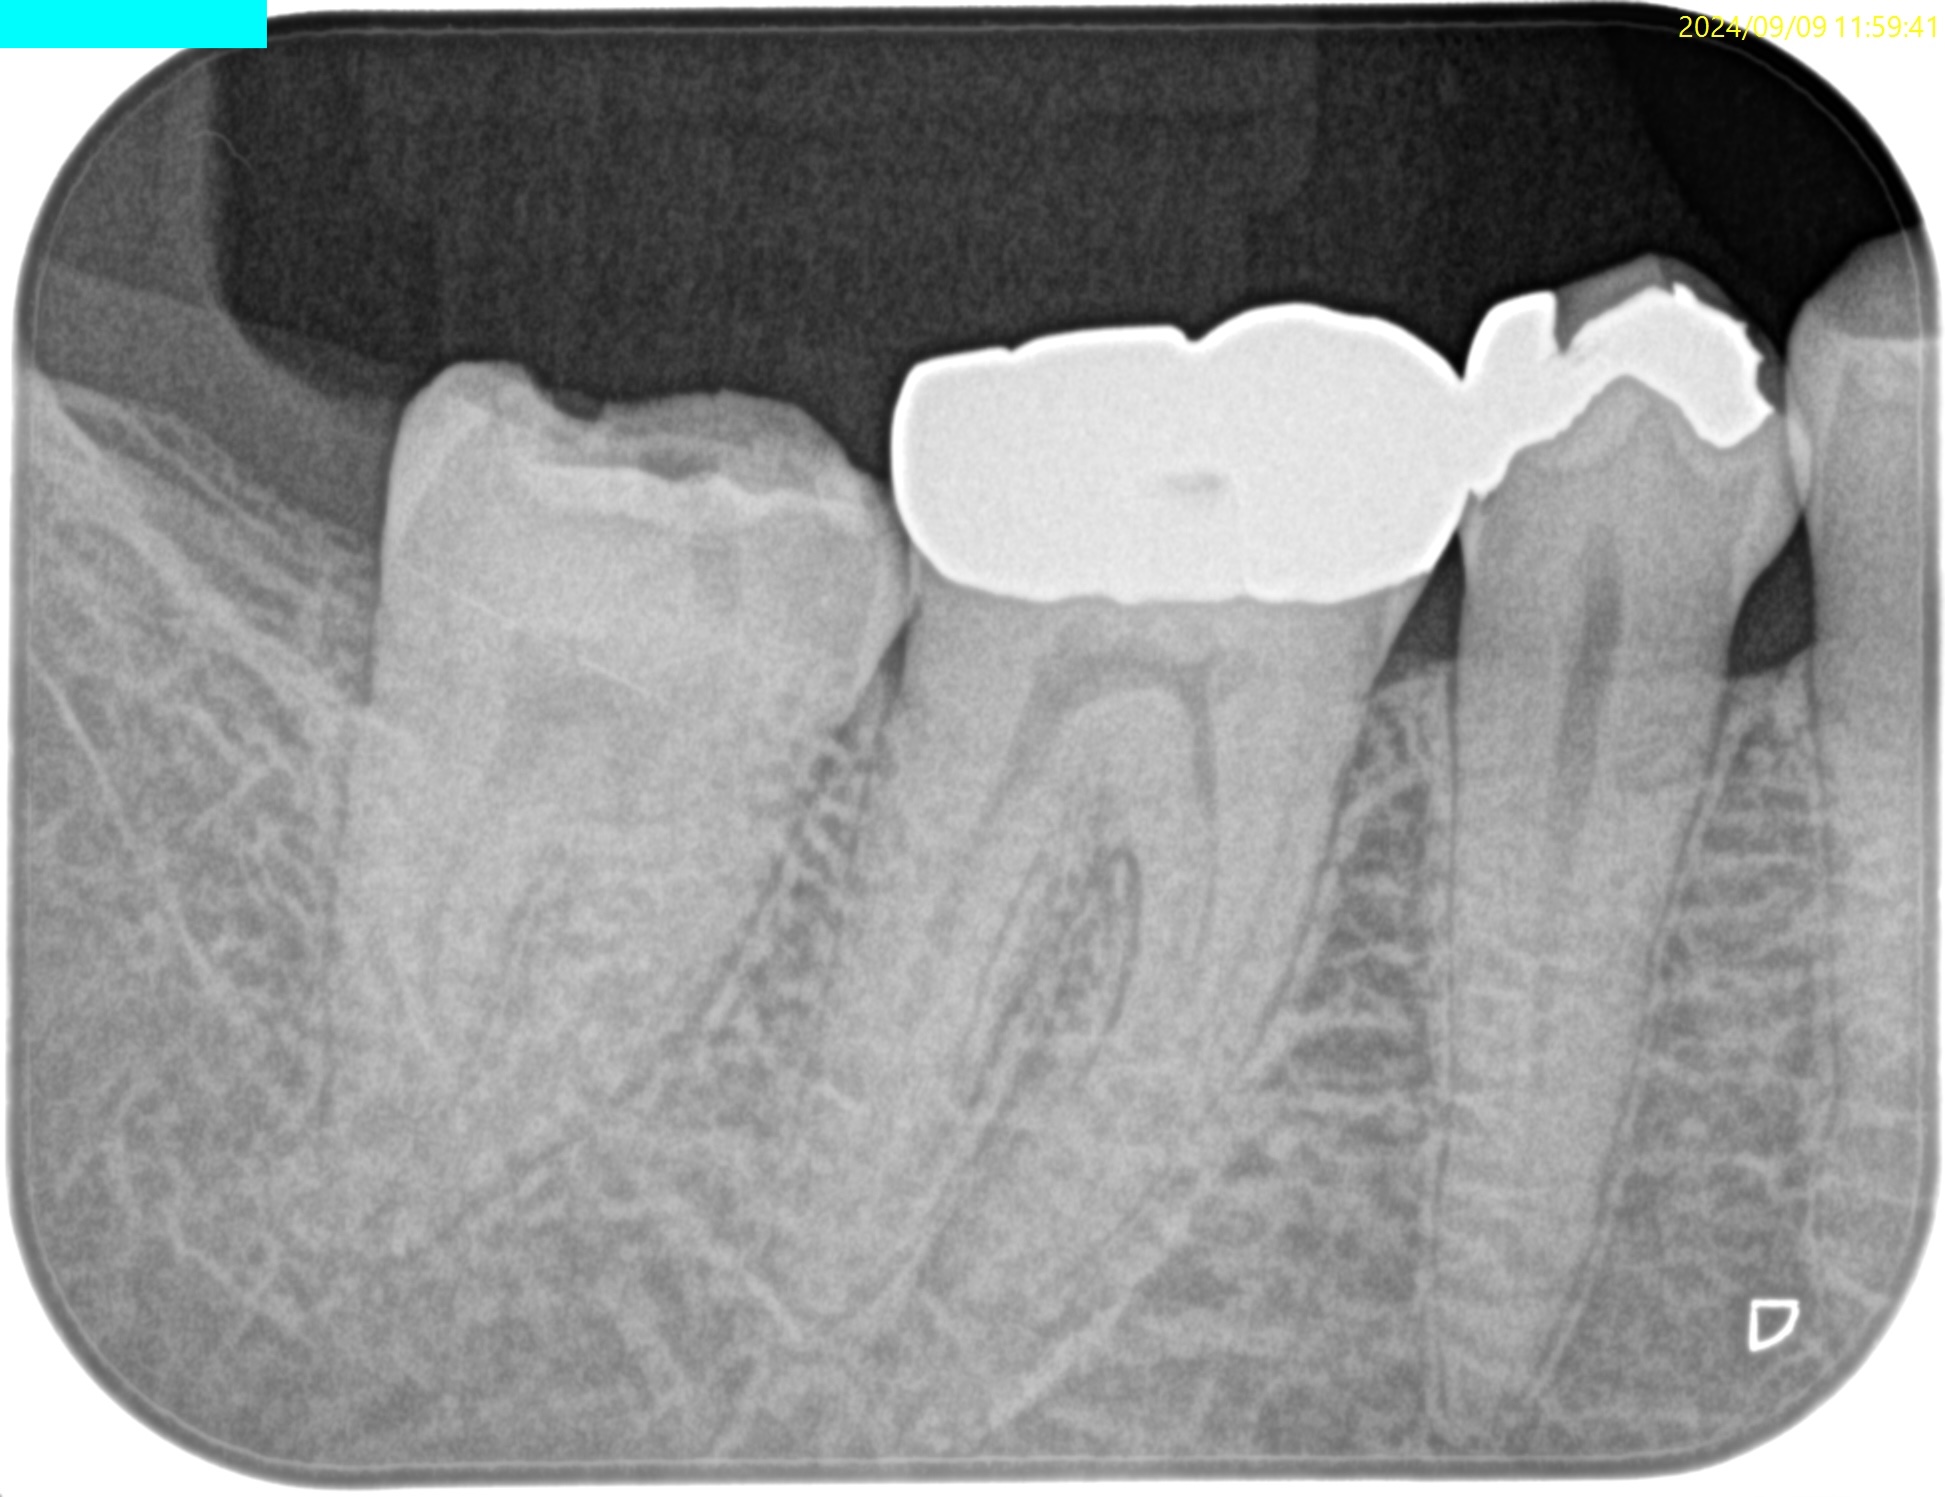

PA(2024.9.9)

他院で#31 Metal Inlayを除去し、レジン充填した状態になっている。

#30 Cold+12/4, Perc.(-), Palp.(-), BT(-), Perio Probe(WNL), Mobility(WNL)

#31 Cold+1/2, Perc.(-), Palp.(-), BT(-), Perio Probe(WNL), Mobility(WNL)